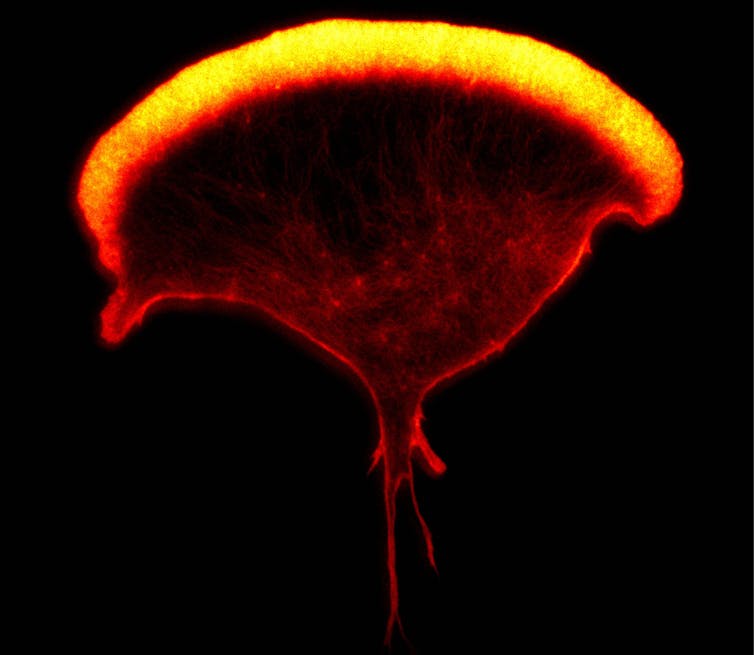

To tackle the issue, a consortium of scientists (co-led by Teichmann as part of the Human Cell Atlas project) analysed around 70,000 cells from the placenta and lining of the womb from women who had terminated their pregnancy at between six and 14 weeks.

The placenta is the organ where nutrients and gases pass back and forth between the mother and developing baby. It was once thought the mother’s immune system must be switched off in the lining of the womb where the placenta embeds, so that the placenta and foetus aren’t attacked for being “alien” (like an unmatched transplant) on account of half the foetus’s genes coming from the father. But this view turned out to be wrong – or too simple at the very least.

We now know, from a variety of experiments including this analysis, that in the womb, the activity of the mother’s immune cells is somewhat lessened, presumably to prevent an adverse reaction against cells from the foetus, but the immune system is not switched off. Instead, the immune cells we met earlier, natural killer cells, well known for killing infected cells or cancer cells, take on a completely different, more constructive job in the womb; helping build the placenta.

The scientists’ analysis of 70,000 cells has also highlighted that all sorts of other immune cells are also important in the construction of a placenta. What they all do, though, isn’t yet clear – this is at the edge of our knowledge.